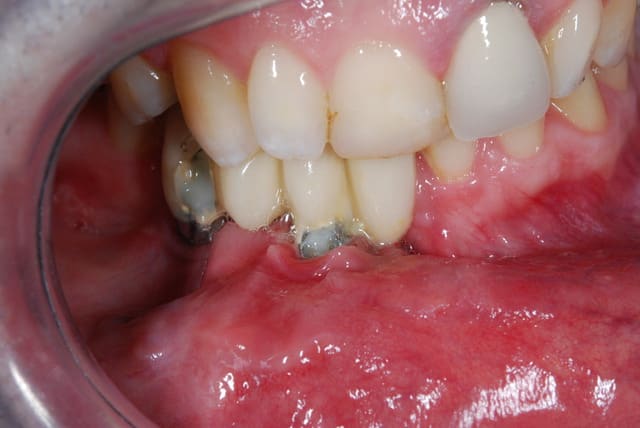

là c'est moins marrant

les deux incisives adjacentes sont très mobiles et douloureuses,l'implant est en place depuis deux ans il y a du tartre de partout

solutions?

> les deux incisives adjacentes sont très mobiles et douloureuses,l'implant est en

> place depuis deux ans il y a du tartre de partout

> solutions?

c'est le même?

seule solution, virer la dernière incisive et faire un bridge avec une dent en cantilever.